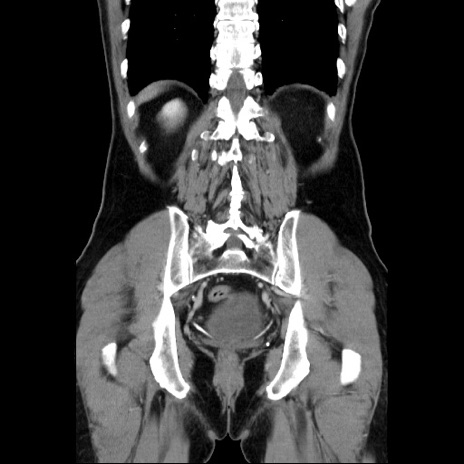

症例34(冠状断像)

【症例】60歳代 男性

【主訴】右鼠径部膨隆

【現病歴】1年程前より右鼠径部膨隆あり。自己にて還納可能だったため放置していた。3時間前より右鼠径部の脱出を認め、還納困難となり受診。

【既往歴】高血圧

【身体所見】右鼠径部に小児頭大の膨隆あり。弾性硬であり、用手還納は困難。左鼠径部にも膨隆を認める。脱出はなし。

【データ】WBC 15500、CRP 測定なし